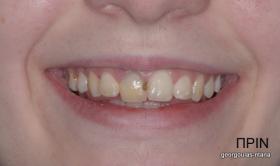

Η κοπέλα αυτή ήρθε στο ιατρείο με κάταγμα στον δεξιό άνω κεντρικό τομέα. Το δόντι είχε απονευρωθεί στο παρελθόν και είχε αποκατασταθεί με βιδωτό άξονα κ ανασύσταση με ρητίνη και το αισθητικό αποτέλεσμα ήταν φτωχό. Η ασθενής ήθελε να είναι καλυμμένη αισθητικά για όσο χρονικό διάστημα θα διαρκούσε η θεραπεία. Πραγματοποιήθηκε τομογραφία κωνικής δέσμης (CBCT) στην περιοχή και αποφασίστηκε να γίνει εξαγωγή του δοντιού, διατήρηση του όγκου του φατνίου και 3 μήνες μετά τοποθέτηση εμφυτεύματος με ταυτόχρονη χρήση μοσχευμάτων σκληρών κ μαλακών ιστών  για βέλτιστο αισθητικό αποτέλεσμα. Το εμφύτευμα αποκαταστάθηκε με υβριδικό κολόβωμα από διπυριτικό λίθιο και ολοκεραμική στεφάνη από διπυριτικό λίθιο (Emax). Καθ’ όλη τη διάρκεια της θεραπείας, η ασθενής ήταν καλυμμένη αισθητικά με γέφυρα Meryland  συγκολλημένη στα δύο διπλανά δόντια. Μετά την οστεοενσώματωση του εμφυτεύματος και πριν την τελική αποκατάσταση, τοποθετήθηκε στο εμφύτευμα προσωρινή εργασία με σκοπό τη βελτίωση των ούλων.